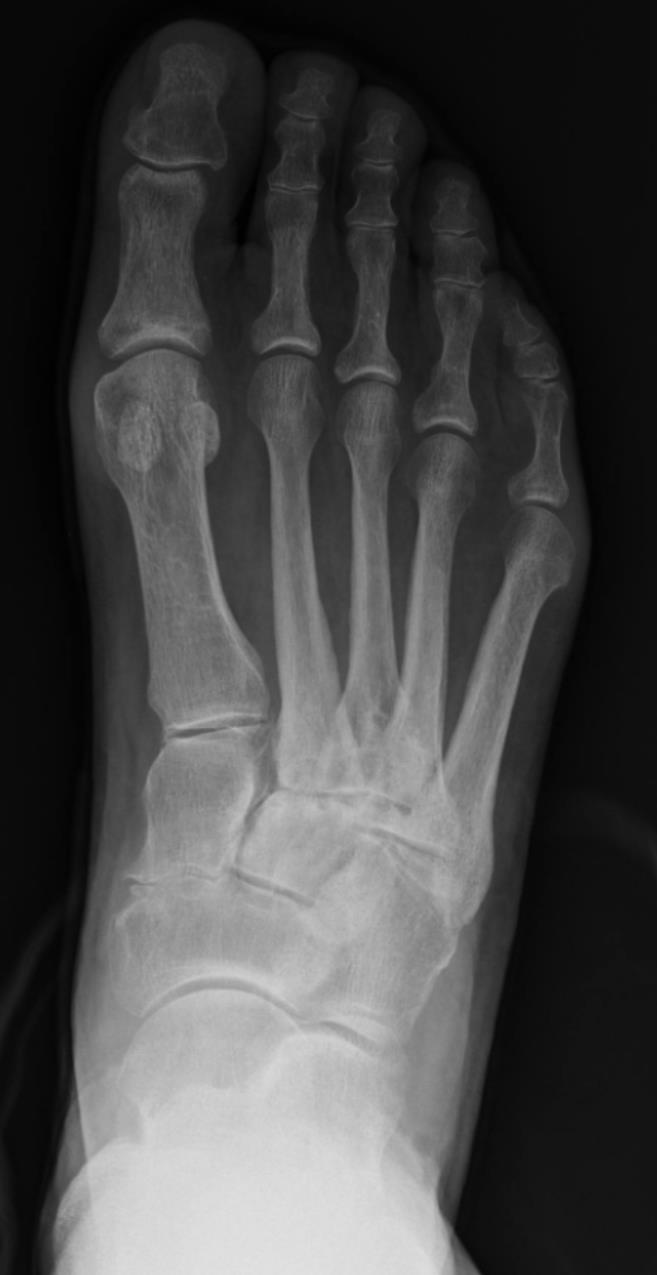

• Avascular necrosis of the first metatarsal head is rare. Although idiopathic cases have been reported, AVN of the first metatarsal head is usually iatrogenic following surgical correction of hallux valgus using a distal metatarsal osteotomy with or without lateral soft tissue release. A thorough understanding of the delicate vascular anatomy of the first metatarsal head is essential when surgery is considered. Careful operative technique permits a safe combination of distal osteotomy and lateral soft tissue release. Because the intraosseous blood supply is completely disrupted with distal metatarsal osteotomy, excessive capsular release and saw blade penetration into the lateral capsular vessels must be avoided. Among the thousands of reported distal metatarsal osteotomies performed using a variety of technique modifications of the original procedure described by Austin, the prevalence of AVN is low. Undoubtedly, the first metatarsal head has an excellent capacity to accommodate to changes in its blood supply. Although radiographic changes are frequently observed in the metatarsal head following a distal metatarsal osteotomy with or without lateral release, rarely do these changes progress to symptomatic AVN. These transient radiographic findings probably represent an adjustment period as the metatarsal head recovers from vascular compromise. Not only is AVN of the first metatarsal rare, but it is rare for it to be symptomatic. Many more cases that are never identified may exist. Management of symptomatic AVN of the first metatarsal head has not been standardized because of the infrequency of this condition. Anecdotal experience suggests that simple activity and shoe modifications may suffice; however, joint debridement and metatarsal head decompression may prove beneficial as they have in the management of other joints more commonly afflicted with AVN. Finally, severe head collapse may be salvaged with MTP joint arthrodesis. In the event that a substantial amount of avascular bone must be removed, consideration can be given to bone block distraction arthrodesis to avoid transfer metatarsalgia.